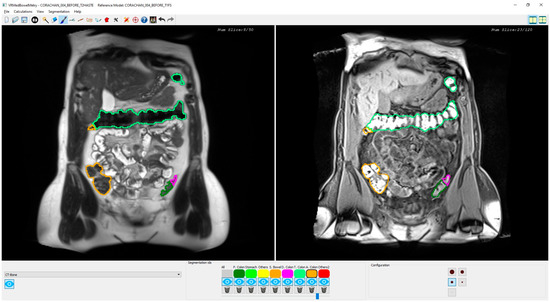

Figure 3.

Snapshot of the synchronized T2 and T1-FS module. On the left side, an original T2 image is shown with the colon segmentation outlined using a different color for each segment. On the right side, the same visualization scheme is used with its corresponding original T1-FS image.

2.3. Synchronized T2 and T1-FS Inspection

As mentioned in Section 1, there may be confusing areas of the colon that require the simultaneous visualization of both modalities to understand the colonic anatomy. Therefore, once both segmentations have been computed, their simultaneous visualization and inspection allows the specialist to analyze, validate, and, if it is needed, to correct the results.

The main novelty of this inspection functionality is that, to our knowledge, it is the first one able to allow synchronous navigation of both MRI sequences considering the deformation suffered in the acquisition process. Note that the original MRI images are visualized without altering them, but the interactive navigation allows computing the corresponding image using the non-rigid transformation matrix. Moreover, the synchronized inspection facilitates a 3D mental reconstruction of the colon in both MRI modalities, which is helpful to validate the segmentation result in both sequences, and the medical expert can modify the colon segmentation, if needed, either in T2 or T1-FS independently. The 3D simultaneous visualization of both segmentations is also possible. However, performing corrections in the 3D space is quite complex and medical specialists prefer the 2D synchronized visualization of T2 and T1-FS images since it provides detailed information about the anatomical structures around the colon and facilitates the validation of the boundaries in the automatically generated segmentations.